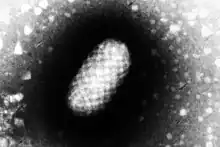

It is caused by a Parapoxvirus.[5] It can occur in humans who handle infected animals or contaminated objects.[2] One third of cases may develop erythema multiforme.[4] Once resolved, a person can still be infected again.[4]

| Orf virus | |

| Genus: | Parapoxvirus |

| Species: | Orf virus |